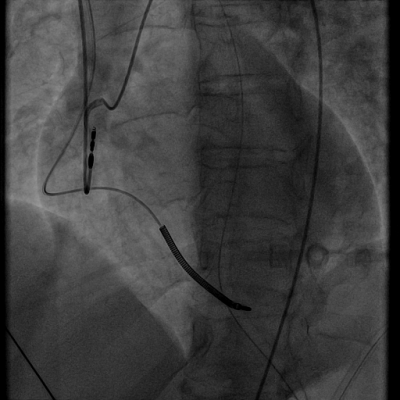

Třiapadesátiletá pacientka sledovaná pro dilatační kardiomyopatii, s diagnózou infarktu myokardu bez elevací úseku ST s normálním koronarogramem v roce 2016, s již implantovaným kardioverterem-defibrilátorem (ICD) v rámci primární prevence náhlé srdeční smrti byla přijata v lednu 2017 na koronární jednotku pro mimonemocniční oběhovou zástavu, které předcházela bolest na hrudi a dušnost. Iniciálním rytmem byla bezpulsová elektrická aktivita (PEA). Pacientce byla poskytnuta standardní resuscitační a poresuscitační péče včetně řízené hypotermie (33 °C, 24hodinový protokol) a terapie přetrvávajícího těžkého šoku. V paměti ICD nebyl záznam maligní arytmie. Akutní koronarografie prokázala normální nález na věnčitých tepnách s výjimkou suspekce na lehký spasmus na pravé koronární tepně (video 1).

Video 1 - Akutní koronarografie prokázala normální nález na věnčitých tepnách s výjimkou suspekce na lehký spasmus na pravé koronární tepně.Echokardiograficky byla zjištěna těžká dysfunkce dilatované levé komory s nezvětšenou pravou komorou (video 2).